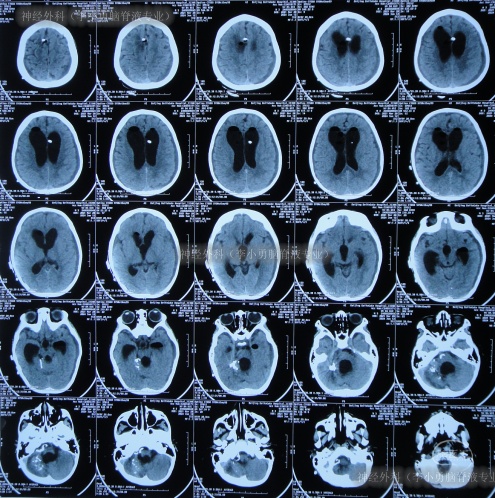

2024年6月3日(脑血管畸形栓塞术后脑积水伴间断高热5月余,外院经5次手术仍脑积水致严重颅内感染)转住入李小勇脑脊液专业,入院时:意识模糊,哭闹,咳嗽伴白色粘痰,高热,鼻饲流食;携带外院脑室外引流管;头部有多处瘢痕,有手术缝合线(图-4);入院时头颅CT示脑室外引流术后、脑积水(图-5)。

图-5:2024年6月3日入院时头颅CT

入院后10天即2024年6月12日,查头颅CT示脑室有所缩小(图-9)。

图-9:2024年6月12日头颅CT

继续治疗近2月,期间2次查头颅CT均示脑室缩小(图-15),且变得能在搀扶下走路(图-16)。

图-15:2次查头颅CT